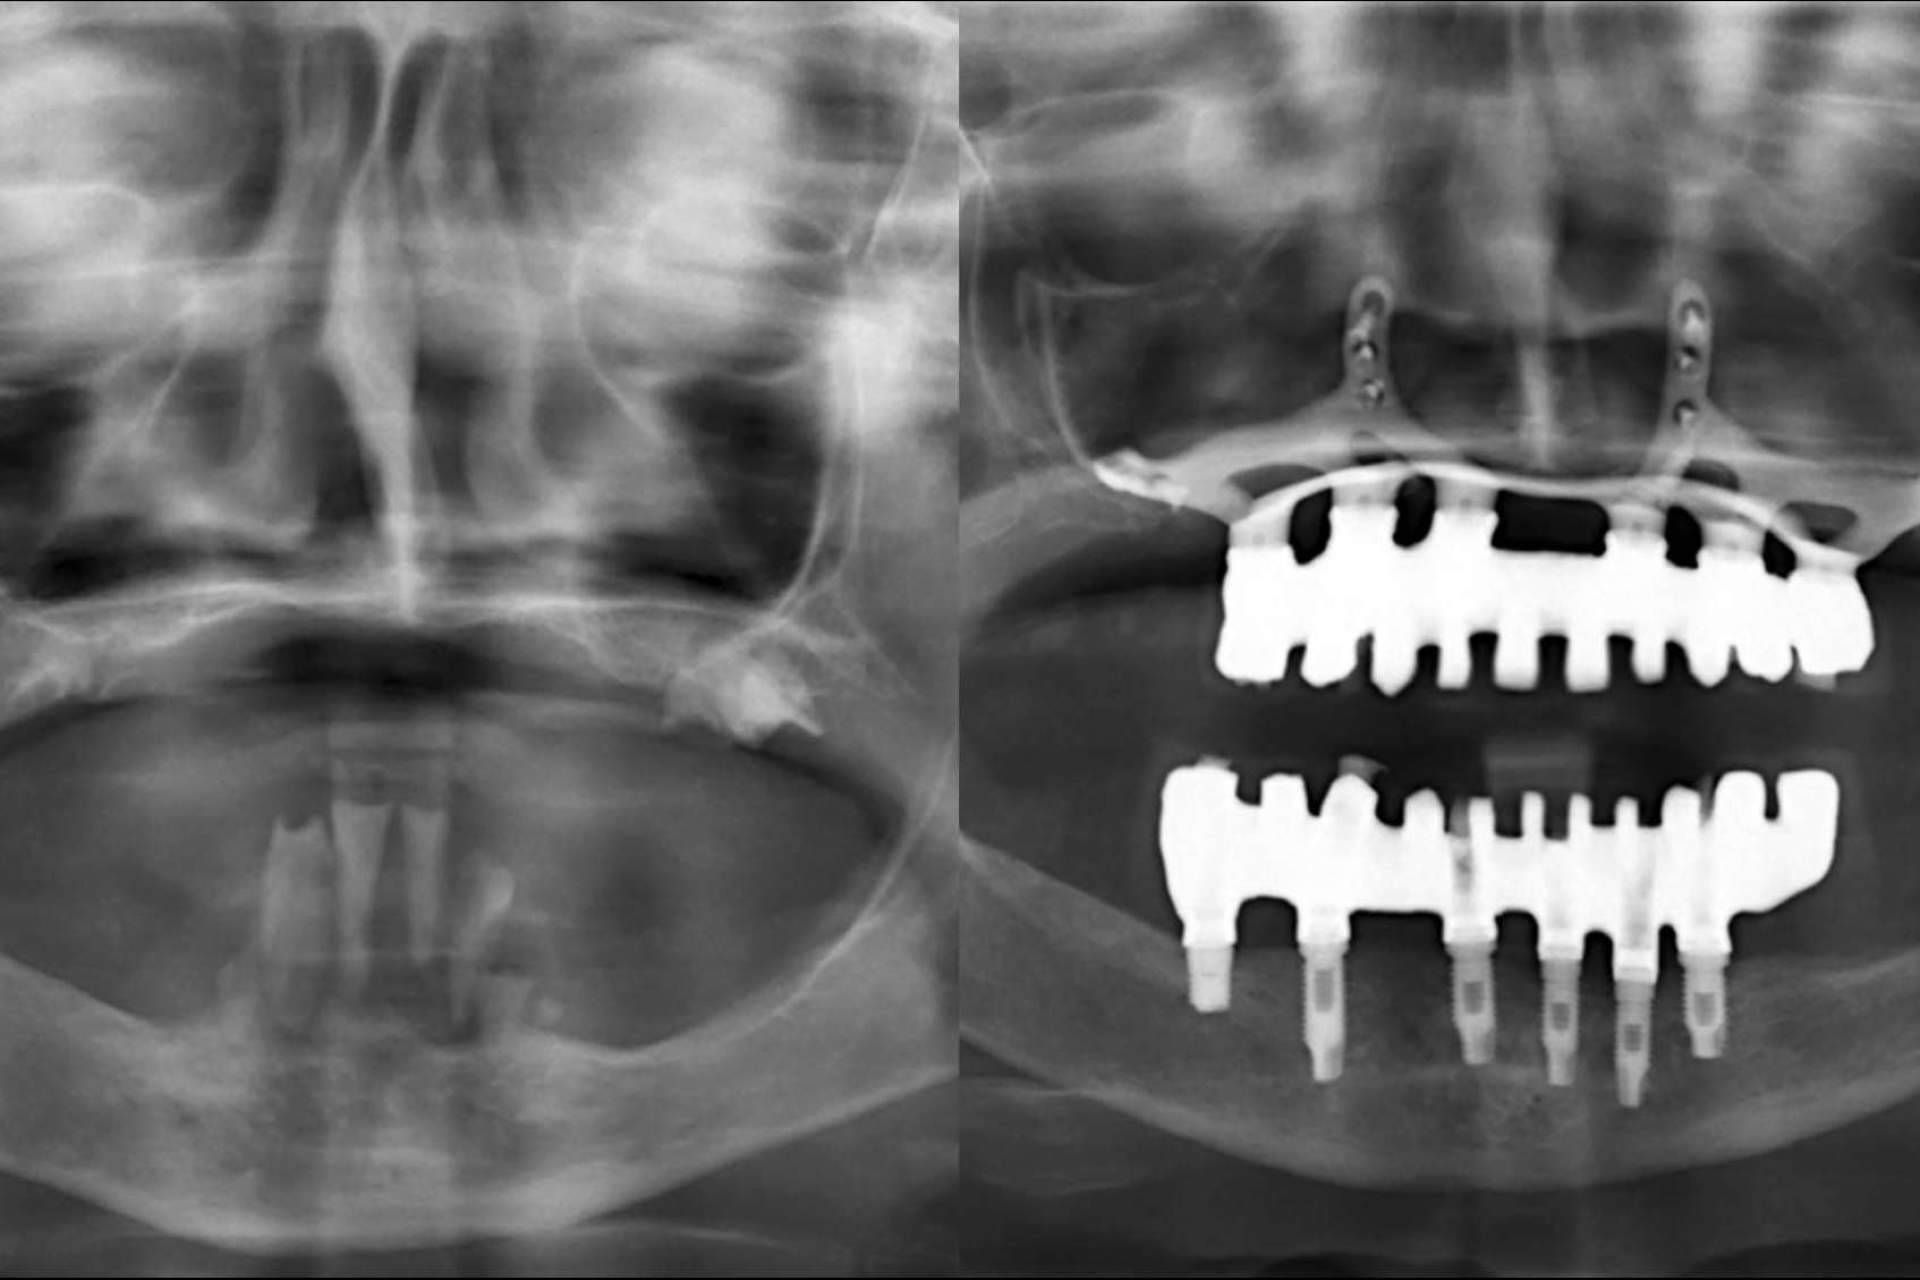

Por otro lado, los cirujanos comenzarán haciéndose una planificación digital y la elección de los materiales regenerativos que mejor se adapten al paciente. Para alcanzar el diagnóstico más preciso, la clínica utiliza tecnología 3D de escáner, con el fin de confeccionar prótesis personalizadas, que pueden ser colocadas en una única intervención.

En los casos más complejos en los que falta la cantidad de hueso ideal, la técnica del injerto óseo es la indicada, al colocar tejido autólogo, tomado del propio paciente; o heterólogo, de otra especie, por lo general la bovina, para contar con un buen soporte del implante, sin rechazo ni reacciones alérgicas. Sin embargo, otros procedimientos que ofrece la clínica son los implantes corticales en caso de atrofia ósea extrema, los implantes cigomáticos y la técnica de elevación de seno maxilar.

Con muchas de estas técnicas se puede recurrir a la carga inmediata, es decir, colocar la prótesis fija pero provisional sobre estos implantes recién colocados.